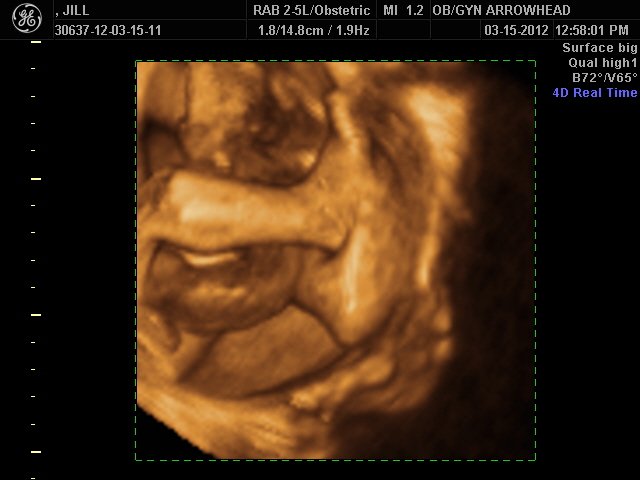

We offer complimentary 3D/4D Ultrasounds to all our OB patients around 30 weeks! The following photos are some examples of our work, shown with permission from our patients.